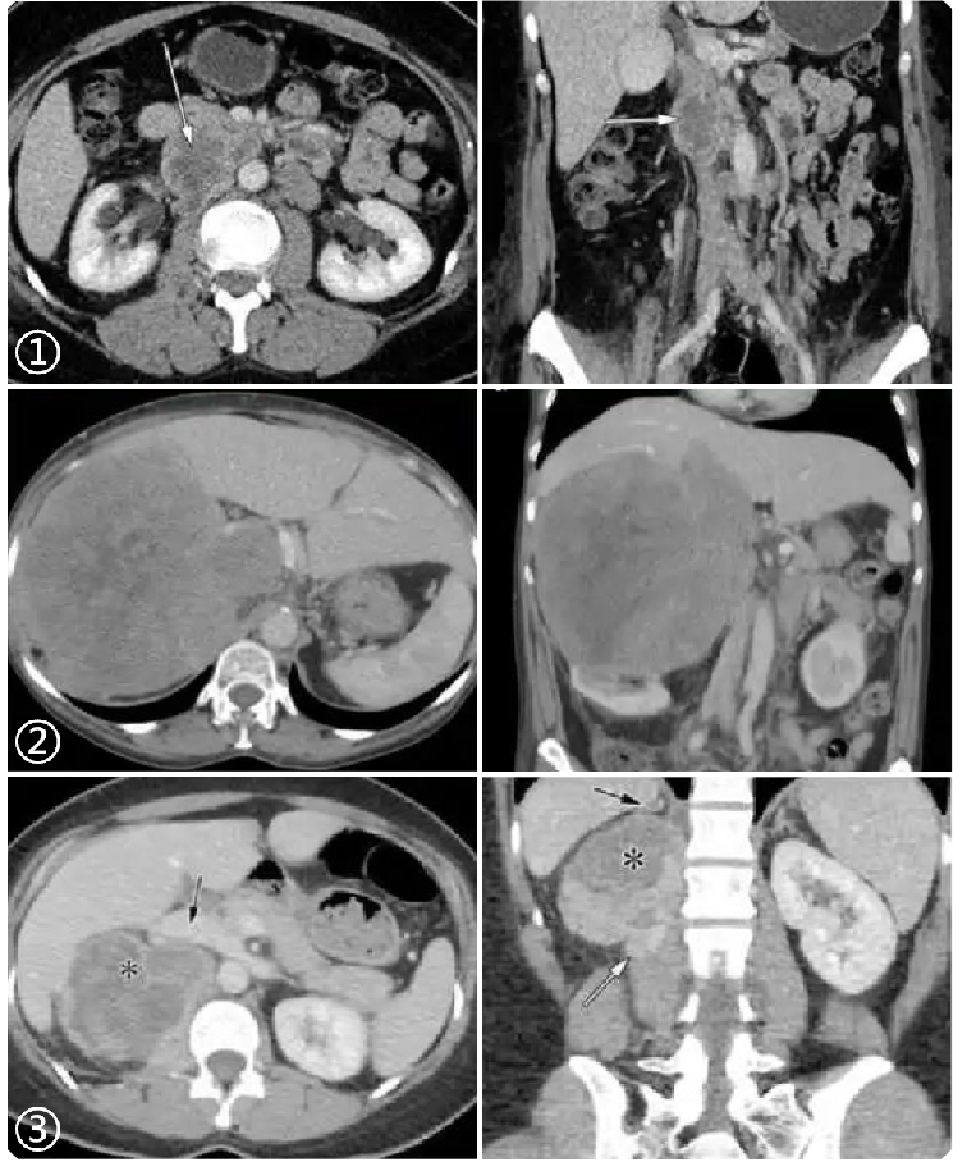

917bfe88330e9a51bacfc381b0a24818.png 病例 6:腹膜后平滑肌肉瘤2例

(① 血管内外;② 血管腔外)① 腹膜后肿块可见侵犯右肾血管、下腔静脉,密度不均匀,有囊变坏死,增强后边缘性延迟环状强化。② 腹膜后肿块与右肾血管,下腔静脉及腹主动脉分界不清,肿块密度不均匀,内可见囊变坏死区及高密度灶(平滑肌肉瘤瘤内如有出血,低密度区内可见高密度出血影,但通常不钙化),增强扫描呈明显不均匀强化,囊变区未见强化。